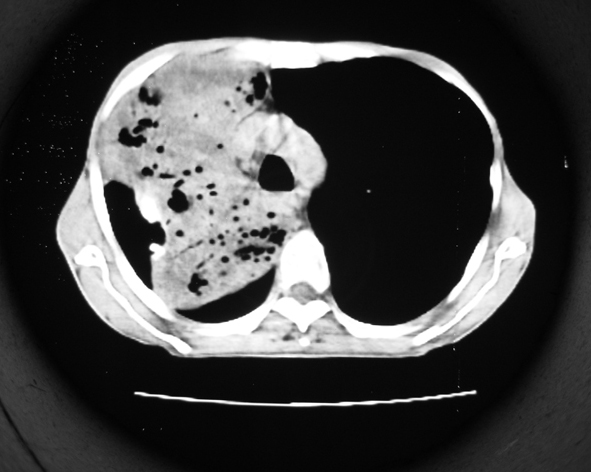

男53岁,咳嗽气短,以往身体健康.

右肺上叶多发多形态空洞及增殖灶,可见团块钙化,胸膜肥厚、粘连,考虑继发型肺结核可能性大

1.右肺上叶干酪性肺炎,2。肺气肿,肺大泡

右肺上中叶结核干酪性肺炎

右肺中上叶干酪性肺炎。